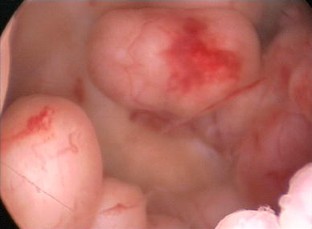

Fig. 1